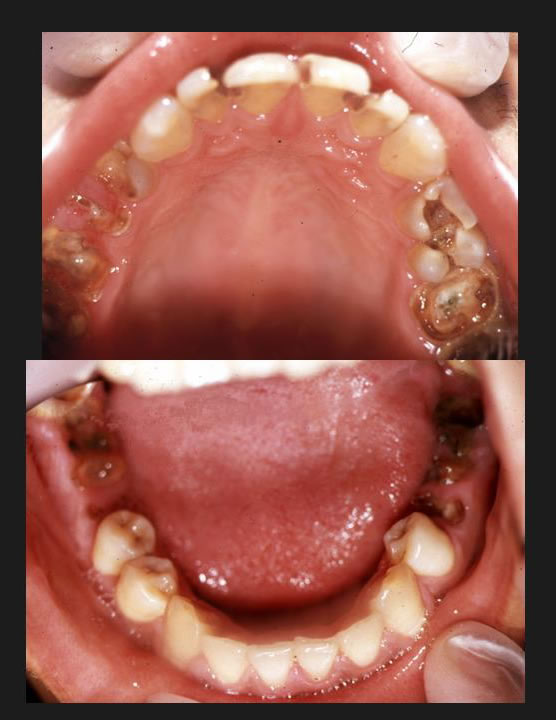

唐突であるが、これは18歳の悲惨な少年の口腔である。(図1)

図1

この歯では、せいぜい前歯でうどんを咬み切って、丸飲みする位の食べ方しかできないだろう。

さて、冒頭で18歳の少年の写真をご覧いただいた。

この写真、実は少年院で撮影したものである。

重い罪を犯した、多くの少年達は、このような口をしていた。